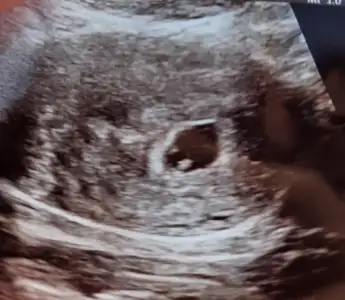

Kızlar merhaba tüp bebek ilk transferimle hamile kaldım. Çok şükür nasip oldu hep burda yazılanları okuyup dua ediyodum. Rabbim bütün tedavi olanlara,isteyenlere nasip etsin inşallah

7.haftama girdim kese,bebek, kalp atışı var. Biliyorum çok erken ama çok merak ediyorum sizce cinsiyeti ne olabilir inanın hiç fark etmez sağlıkla olsun ama inanın içim kıpır kıpır çok merak ediyorum. Kesenin sekline yada bebegin sağ sol durumuna göre bileniniz var mı acaba